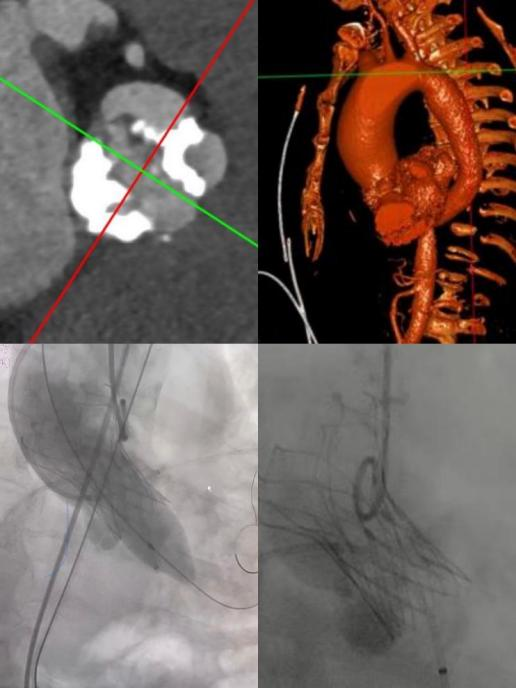

72岁老年男性,阵发性胸闷、憋喘入院,夜间难以平卧。陈玉国教授TAVI团队紧急对患者做术前评估与准备,术前心脏彩超:LVEF 0.38,二叶式主动脉瓣(TypeI型),主动脉瓣硬化并狭窄(重度);术前CT可见瓣叶重度钙化(钙化积分大于1600分),升主动脉瘤样扩张(平均径57mm),且横位心,术中存在升主动脉瘤破裂风险,冠脉开口堵塞风险高(左冠开口高度6.8mm)。

61岁老年女性,活动后呼吸困难入院,入院后心脏彩超示:LVEF 0.39,二叶式主动脉瓣(TypeI型),主动脉瓣狭窄(重度),CT可见瓣叶严重钙化(钙化积分 1300分),左冠开口高度12mm,瓣叶长近15mm,同样存在冠脉开口堵塞风险,同时患者合并重度阻塞性通气功能障碍,外科开刀手术风险大。

两例患者均心脏功能差,心衰症状频发,二叶式主动脉瓣合并瓣叶严重钙化,升主动脉瘤样扩张,冠脉开口位置低,手术操作难度大,风险极高。在陈玉国教授的指导下,急诊科李传保教授带领TAVI团队在多学科的协助配合下,一站式完成冠脉造影,主动保护左冠状动脉,经股动脉成功置入主动脉瓣膜,术后超声显示主动脉瓣跨瓣压差降至5-10mmHg,无明显反流及瓣周漏,支架形态完美,心功能显著改善。出院前复查心脏彩超,心脏射血分数(LVEF)分别由38%、39%提高至61%及71%,术后3天康复出院,大大缩短了平均住院日。